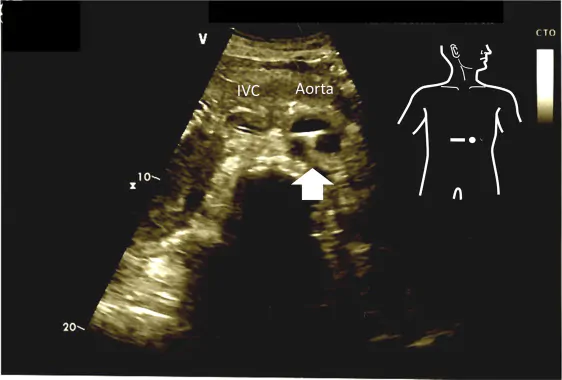

- Установите датчик в середине верхней части живота и сканируйте аксиальное изображение 2-й зоны брюшной аорты, которая обычно расположена перед поясничным позвонком.

- Прижмите датчик по направлению к брюшной стенке, в случае если не сканируется четкое изображение (через газ в желудке или поперечно ободочной кишке). При нажатии на датчик газ под датчиком освобождается и сканируется четкое изображение. Если проводник находится во 2-й зоне брюшной аорты, проводник также сканируется.

- После сканирования аксиального изображения брюшной аорты датчик поворачивается на 90° по часовой стрелке и сканируется сагиттальное изображение.